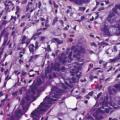

La classification des cancers gastriques est complexe puisque plusieurs types histologiques peuvent coexister au sein d’une même tumeur. Par ailleurs, différentes classifications histologiques sont utilisées en pratique courante et dans les études, avec des valeurs pronostiques variables. L’adéno- carcinome gastrique à cellules indépendantes (ADCI) est défini comme étant un adénocarcinome gastrique comportant un contingent majoritaire (plus de 50 % de la tumeur) de cellules isolées ou de petits groupes de cellules disséminées dans un stroma particulièrement fibreux et contenant de la mucine en intracytoplasmique (fig. 1) [v. encadré2, 3]. Il a une épidémiologie et un pronostic propre. Il est, en effet, plus fréquemment observé chez les sujets jeunes et est diagnostiqué à un stade plus avancé que les autres types histologiques. Il est également associé à un pronostic plus sombre, que ce soit sur la survie globale ou la survie sans récidive.4

L’examen anatomopathologique de la pièce opératoire montre l’existence d’un adénocarcinome peu différencié de l’antre gastrique, de 42 x 23 mm, avec un contingent majoritaire de cellules isolées en bague à chaton (60 %) dans un stroma fibreux. La lésion est classée pT3N1Mx. La réponse à la chimiothérapie préopératoire est moyenne, estimée selon la classification de Mandard à TRG3. Les marges de résection sont saines d’envahissement tumoral (R0).